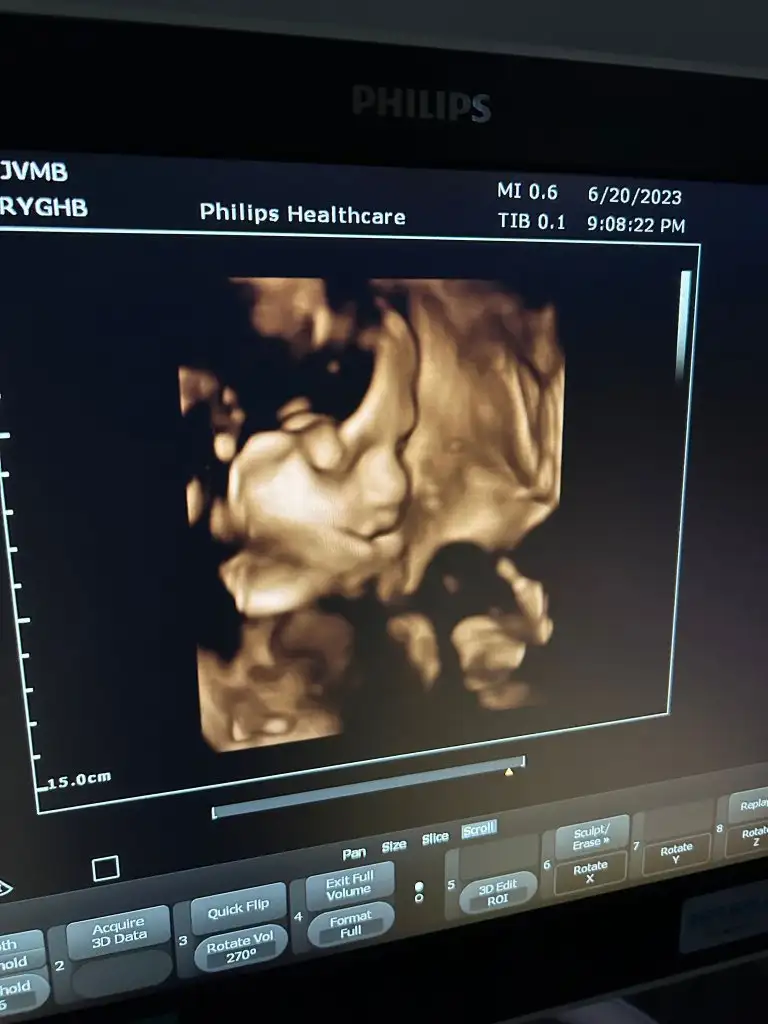

ha bir de fiziki yapım normal doğuma müsaitmiş ve her geldiğinde rahim ağzı uzunluğuna bakıyorum gayet iyi erken doğum riski falan yok dedi ( bunu eşim sordu risk var mı diye )selam teyzoşlar bizim bugün kontrolümüz vardı çok şükür her şey yolunda, geçen ay suyuma biraz fazla demişti bebekte 1 hafta öndeydi ama bu ay her şey yoluna girmiş suyuma çok iyi dedi bebekte haftasıyla uyumlu ama bacak boyu uzun dedi normalde bugün 28+1 im ölçümde 29+0 çıkıyordayı ve teyzelerine çekmiş bu konuda onun dışında benimde tüp bebek doğum için ne düşünüyorsunuz dedim normalde tüp Bebek anneleri riske atmaz sezaryen isterler ama normal doğuran 5 6 hastam da oldu dedi, artık bakacağız duruma göre her şey yolundaysa bende normal istiyorum , bunun için ne yapmalıyım birşey öneriyor musunuz diye sordum şu an bir şey yapma 34 ten sonra pilates, pelvik taban egzersizlerine vs başlarsın dedi, ımm onun dışında CLEXANE ı doğuma kadar kullanacağım ha bu arada hep unutuyordum bu sefer boyunu sordum 36 37 cm dedi yaklaşık bu bebişimizin fotosu zor gösterdi yüzünü babası da ona benzemiyor diye üzgün